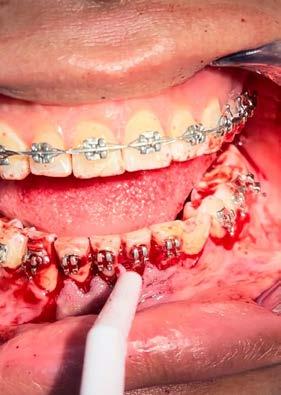

Se tomó impresiones para elaboración de pistas planas especiales con arco de Eschler y tornillo de expansión sagital para proyectar la

premaxila, colocado en enero del 2023, activando un cuarto de vuelta por semana hasta alcanzar expansión de 6 mm. retirando el aparato en un tiempo de 6 meses, dándose de alta temporal en junio del 2023 por 1 año (Figura 5). En julio del 2024, el paciente ya a sus 17 años, acude a su cita de control, se solicitó radiografía lateral de cráneo y su pudo observar que existe una estabilidad en la corrección ósea de la mordida cruzada anterior (Figura 6).

Discusión

El síndrome clase III constituye un reto en el manejo clínico, el éxito en su tratamiento depende de un adecuado diagnóstico, de la intervención oportuna y la colaboración del paciente.16

Hay diferentes tipos de tratamiento para abordar la corrección de la mordida cruzada anterior, dispositivos fijos como plano inclinado inferior y superior, pistas directas o colocación

Tratamiento de mordida cruzada anterior

de corona de acero, aparatología removible como son el Bimler C, pistas indirectas planas, que se utilizan tanto en dentición primaria, mixta y permanente.17 La máscara facial, utilizada a temprana edad, se combina con aparatos ortopédicos removibles, obteniendo una mayor estabilidad en el resultado de la corrección de la mordida cruzada anterior.18

Uno de los objetivos del tratamiento temprano es eliminar el

Figura 5. Cita de julio del 2024. A) y B) Aparato ortopédico encapsulado con tornillo de expansión anterior, observándose el arco de Eschler. C) Oclusión de los incisivos anteriores al inicio del tratamiento.

D) Oclusión de los incisivos anteriores al término de la utilización del encapsulado.

Figura 6. Comparativa radiográfica.

A) Rx. lateral de inicio del tratamiento.

B) Rx. lateral 7 años después.

C)Fotografía de perfil 7 años después.

desplazamiento funcional y así propiciar un medio ambiente en el que pueda haber un desarrollo dentofacial más favorable.19

Conclusión

Podemos determinar que es de suma importancia que el estomatólogo este informado de los factores que involucran la mordida cruzada anterior, para su intervención a edad temprana, ya que de manera preventiva existen técnicas no invasivas para eliminar interferencias o bloqueos dentales. Una vez determinado el diagnóstico se utilizan diferentes aparatos ortopédicos para lograr la armonía y la

funcionalidad de los maxilares evitando que el problema se degenere a un diagnóstico de clase III esquelética y verse en la necesidad de una cirugía ortognática para su corrección.

En caso de no ser tratado este tipo de padecimiento orofacial, habrá afectaciones dentales, de soporte, neuromusculares y faciales. Dentro de un tratamiento estándar de ortodoncia, los movimientos que se generan en su mayoría son dentoalveolares, teniendo como alternativa solo un camuflaje, de tal manera que no tendríamos una remodelación ósea completa en comparación a la utilización de ortopedia maxilar.

Referencias

1. Rodríguez, P. E., Estrada, M. A., & Abraham, M. (2017). Tratamiento de la maloclusión clase III con protracción maxila: reporte de caso. Revista Estomatológica Herediana, 180-190.

2. Reyes, A., & Herrero, Y. (2021). Características morfológicas del síndrome clase III. Segundo Congreso Virtual de Ciencias Basicas Biomédicas en Grandma. Manzanillo, 1-13.

3. Mato, A., Peréz, L., Rodríguez, M. D; & González, A. (2016). Mordida cruzada anterior y tratamiento en la atención primaria. Revista de Ciencias Médicas de Pinar del Río, 88-98.

4. Cabrera, T. V., George, Y., Martínez, M. R., Ramírez, Y., & González, L. (2016). Estado de la oclusión y tratamiento selectivo en niños con dentición temporal y mixta temprana. Medisan, 1-10.

5. Ruíz, C. D., & Saéz, G. (2015). Corrección de mordida cruzada anterior con ortopedia. Revista Mexicana de Ortodoncia, 239-248.

6. Cameron, A., & Widmer, R. (1998). Diagnóstico y tratamiento ortodoncico en la fase de dentición mixta. Manual de odontología Pediátrica, España: Harcourt Brace. 267-287.

7. Suárez, J. (2000). Odontología en atención primaria. Diagnóstico de las Maloclusiones en atención primaria. Barcelona: Instituto Lacer de Salud Bucodental. 49-76

8. Reni, K. & Piñeiro, S. (2014). Malos hábitos orales: rehabilitación neuromuscular y crecimiento facial. Revista Médica Clínica Las Condes, 380-388.

9. Ramírez, J., Muñoz, C., Gallegos, A., & Rueda, M. A. (2010). Maloclusión clase III. Salud en Tabasco, 944-950.

10. López, D. F., & Corral, C. M. ( 2015 ). Abordaje terapéutico de la maloclusión de pseudoclase III. Reporte de caso clínico. Revista Mexicana de Ortodoncia, 249-256.

11. Ojeda, R. E., Galiana, A. V., Lértora, M. F., Amarilla, M. E., Briend, M. R., Elizondo, M. L., y otros. (2018). Desgaste selectivo de caninos. Facultad de Odontología, 1-7.

12. Ubilla, W., Sánchez, M., Mazzini, F., & Moreira, T. (2017). Tratamiento con cirugía ortognática en paciente clase III esqueletal, con laterodesviación mandibualr izquierda. Odovtos International Journal of Dental Sciences, 15-24.

13. Gamez, A., & Velázquez, J (2016). Frecuencia de maloclusiones en pacientes con dentición mixta de la clínica de la Especialidad en Odontopediatría de la Universidad Autónomade Sinaloa. Revista Tamé, 482-484.

14. Rakosi, T., & Irmtrud, J. (1992). Atlas de ortopedia maxilar diagnóstico, Clasificación de las malposiciones. Nomenclatura Barcelona: Masson-Salvat, 35-56.

15. Isper, G. A., Wakayama, B., Adas, S. T., & Adas, S. G. (2020). Intervención temprana de la mordida cruzada por la pista directa de planas: relato de siete años de seguimiento. Ciencias de la salud, 1-10.

16. Martínez, M. C., Rodríguez, L., & García, D. (2019). Resultado terapéutico con pistas planas en el síndroe de clase III, . Estomatología2020, 1-2.

17. Espasa, J. E., Boj, J. R., & Ustrell, J. M. (1994). Aproximación al tratamiento precoz d la mordida cruzada anterior. Anales de Odontoestomatología, 74-79.

18. Hernández, J., & Soto, L. (2006). La máscara facial de protracción en el tratamiento tempano de la maloclusión clase III. Revista estomatología, 6-11.

19. Hernández, J., & Padilla, M. (2011). Tratamiento temprano de la mordida cruzada anterior. Revisión de la literatura. Revista Estomatología, 40-47.

Trasplante dental autólogo complementario al tratamiento ortodóntico

Para los especialistas en ortodoncia y ortopedia los dientes retenidos representan un reto que no siempre lleva el tratamiento a preservar dichas piezas dentales, al contrario, se opta por su extracción debido a la imposibilidad de trasladarlos a su lugar anatómico con movimientos propios. Se expone el caso clínico y el manejo interdisciplinario de un trasplante dental autólogo, cuidando cada detalle clínico, bilógico e histomorfológico, para ser considerado como una alternativa de dientes retenidos durante un tratamiento de ortodoncia. El caso presenta un paciente de 30 años de edad con aumento de volumen en la zona anterior mandibular a nivel de ápices de los dientes anteriores y asociado a un canino retenido. Clínicamente se observa

persistencia inusual del diente 73; el estudio radiológico confirma un diente colocado transversalmente en relación a los dientes presentes adyacentes. Se realiza odontectomía convencional, preparación alveolar como lecho receptor, odontectomía por disección del 33 y trasplante de este a la zona anatómica correspondiente para devolver la funcionalidad estomatológica del arco dental mandibular y biorreconstrucción alveolar del defecto óseo postextracción. A los 90 días de la cirugía se observa clínicamente y radiográficamente características de cicatrización dentoalveolar con tripodismo funcional.